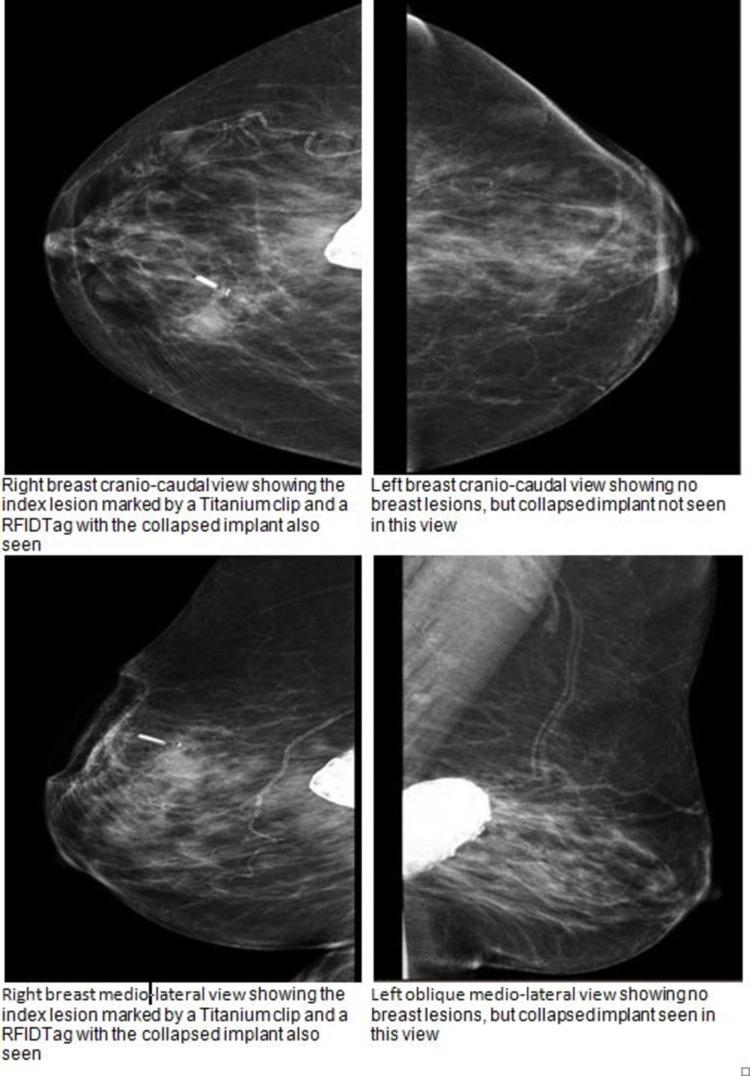

Breast augmentation has been gaining popularity over the last two decades to correct congenital breast asymmetry or increase breast size and projection. Augmentation options started with saline implants, then silicone implants, and, recently, autologous fat transfer. Unfortunately, breast implants are not without complications, some of which are common, like capsular contracture, implant failure and infection. Others are quite rare, such as Breast Implant-Associated Anaplastic Large Cell Lymphoma (BIA-ALCL). Most of these complications will eventually require explantation in most cases, as the patients' and implants' age and risk of complications increase. We present a 79-year-old patient who presented to our breast unit with a left breast lump with 50-year-old saline implants. A triple assessment revealed incidental right breast cancer treated with radiofrequency identification (RFID) tag-guided wide local excision, sentinel lymph node biopsy and bilateral explantation.

在过去二十年中,隆胸手术越来越受欢迎,用于矫正先天性乳房不对称或增加乳房大小和凸度。隆胸的选择最初是盐水植入物,然后是硅胶植入物,最近则是自体脂肪移植。不幸的是,乳房植入物并非没有并发症,其中一些很常见,如包膜挛缩、植入物失效和感染。其他则相当罕见,如乳房植入物相关间变性大细胞淋巴瘤(BIA-ALCL)。在大多数情况下,随着患者和植入物的年龄以及并发症风险增加,这些并发症中的大多数最终都需要取出植入物。我们介绍了一位79岁的患者,她因左乳房肿块来到我们的乳腺科,其乳房中植入了已有50年历史的盐水植入物。三重评估发现了偶然的右乳癌,通过射频识别(RFID)标签引导的广泛局部切除、前哨淋巴结活检和双侧植入物取出进行了治疗。